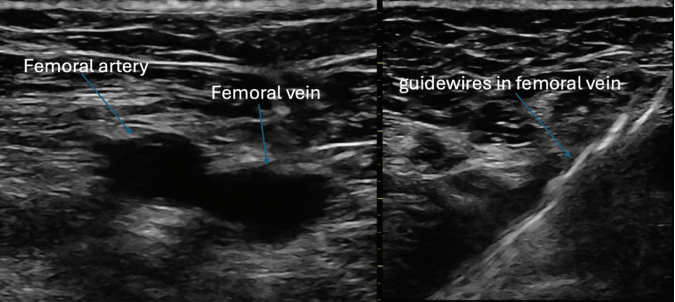

diagnosed 1.5 years prior. He was previously cardioverted and maintained on dronedarone with recurrence of symptomatic persistent AF, prompting referral for catheter ablation. He subsequently underwent AF ablation utilizing a pentaspline catheter. Ultrasound guidance was utilized to obtain 3 points of vascular access in the right femoral vein (Figure 1). ICE guidance was utilized for transseptal access and to guide catheter manipulation while ensuring optimal contact with ablation (Figures 2 and 3). Meticulous sheath management was employed, ensuring performance of all sheath exchanges while aspirating to reduce likelihood of air bubble introduction. A baseline electroanatomic voltage map was obtained for a substrate-based approach, which showed a predominantly healthy left atrium despite persistent AF though notably early in its course (Figure 4). There was spontaneous induction of AFL with a cycle length of ~280 ms and response to entrainment and activation mapping most consistent with typical AFL. The decision was made to proceed with PV isolation with confirmation of antral level isolation without significant encroachment on the posterior wall on a post-ablation voltage map (Figure 5). The cavotricuspid isthmus line was outlined on the EAM system with ICE while ensuring the intended ablation path was not in direct proximity to the right coronary artery. Ablation was then performed utilizing the pentaspline catheter in flower configuration after pre-administration of nitroglycerin and phenylephrine with termination of AFL and demonstration of bidirectional block post ablation. Total fluoroscopy time was ~4 minutes, the majority of which was utilized for the typical flutter ablation. The patient tolerated the procedure well and was discharged home 6 hours later. He continues to do well in outpatient follow-up.

Highlighted in this case are key tenets in our procedural approach to PFA. First, similar to other ablation technologies, the majority of complications are usually vascular in origin. These complications are largely mitigated with appropriate ultrasound guidance technique to vascular access, as was demonstrated in the MANIFEST-17k registry.16 The need for meticulous sheath management to reduce air bubble introduction cannot be overstated given the large sheath profiles utilized, to reduce the risk of stroke and coronary air embolism. We maintain that ICE guidance and EAM play a pivotal role in guiding ablation. This is important to ensure adequate contact for optimal energy delivery as there is increasing data highlighting its importance for durability.17